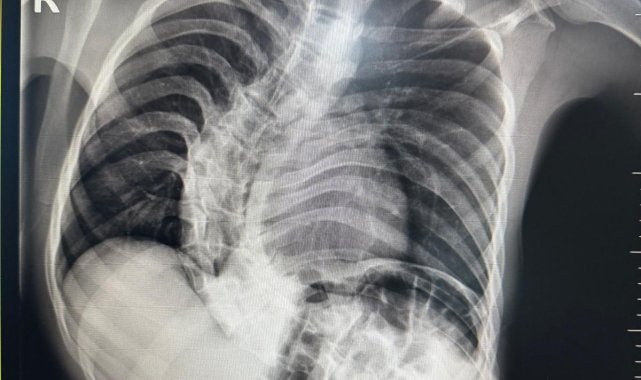

Kırgızistan'da 18 yaşına kadar skolyozla mücadele eden genç, Medicana Hastanesi'nde geçirdiği başarılı ameliyatın ardından sağlığına büyük ölçüde kavuştu.Skolyoz hastalığıyla mücadele eden 19 yaşındaki Shakhbos Pochokalonov, tedavi olmak için ülkesi Kırgızistan'dan Türkiye'ye geldi. Yaklaşık bir sene önce Ankara'ya gelen Pochokalonov, burada Medicana hastanesine başvurarak, tedavi sürecini başlattı. Pochokalonov, Medicana Sağlık Grubu bünyesindeki hastanede gerçekleştirilen operasyonla sağlığına kavuştu.Başarılı geçen ameliyat sonrası hastanın yaşam kalitesinin önemli ölçüde arttığını belirten Ortopedi ve Travmatoloji uzmanı Prof. Dr. Mehmet Atıf Erol Aksekili, skolyoz hakkında bilgi vererek, "Skolyoz kısaca omurganın S şeklini almasıdır. Ön-arka planda omurganın S şeklini almasını biz kısaca skolyoz diyoruz. Skolyoz en sık adolesan dediğimiz ergenlik döneminde görülür. Ancak diğer hastalıklarla birlikte görüldüğünde daha ileri seviyelerde karşımıza çıkabilir. Hastamız 18 yaşında bize başvurdu. Nöromüsküler skolyoz dediğimiz, nörolojik hastalıkların eşlik ettiği bir skolyoz tipi mevcut. Bu skolyozlar erken yaşta ortaya çıkar ve daha hızlı ilerler. Bu yüzden hastamız bize 90 dereceden daha ileri bir seviyede başvurdu" dedi."Erken teşhis tedaviyi kolaylaştırır"Erken teşhis edilmesi halinde daha az cerrahi ile daha iyi sonuç alınabileceğini belirten Aksekili, "Skolyoz erken tanındığında fizik tedavi, egzersiz ve korseleme gibi yöntemlerle ilerlemesini kontrol altına alabiliyoruz. Hastamızda ileri skolyoz olduğu için iki aşamalı cerrahi uygulandı. İlk aşamada Halo Femoral traksiyon yöntemiyle skolyoz kısmen düzeltildi. İkinci aşamada ise vidalar, rodlar ve osteotomi ile omurga düzeltildi" diye konuştu."Ameliyat sonrası süreç en az ameliyat kadar önemli"Ameliyat sonrası sürecin en az ameliyat kadar önemli olduğuna dikkati çeken Aksekili, omurganın uygun pozisyonda kaynamasının hedeflendiğini belirtti. Hastanın üç ay boyunca dorsolomber korse kullanması gerektiğini söyleyen Aksekili, "Yürümesi öneriliyor ancak ağır yük taşımaması gerekiyor. Yüzme gibi sporlara kısa sürede başlayabilir. Kaynama sürecinde diyetine dikkat etmeli ve 6 hafta ile 3 aylık periyotlarla kontrolleri yapılmalıdır. Kaynama istenilen şekilde ilerlemezse ek müdahaleler veya destek tedavileri uygulanabilir" açıklamasında bulundu."En yakın sağlık merkezine başvurulmalı"Erken teşhisin önemine vurgu yapan Aksekili, "Erken teşhis oldukça önemlidir. Nöromüsküler skolyozlar tamamen engellenemese de özellikle ergenlik dönemindeki skolyozlar uygun postür, egzersiz ve fiziksel aktivitelerle önlenebilir. Omuz ve kalça asimetrisi ya da öne eğilince kaburgada çıkıntı gibi belirtiler fark edildiğinde en yakın sağlık merkezine başvurulmalıdır" ifadelerini kullandı."Doktor öneriyorsa mutlaka ameliyat olunmalı"Baba İlhom Pochokalonov, ise oğlunun ilk teşhisini doğumundan bir yıl sonra fark ettiklerini belirterek, "18 yaşına kadar Kırgızistan'daki doktorlara gittik. Doğumsal skolyoz olduğunu, ameliyat olursa felç kalabileceğini söylediler. Skolyoz ile mücadele eden ailelere önerim, erken teşhis ve doğru zamanda ameliyat. Doktor öneriyorsa mutlaka ameliyat olunmalı. Biz Türkiye'ye geldik, ameliyat olduk ve şifa bulduk. Doktorlara çok minnettarız" ifadelerine yer verdi.